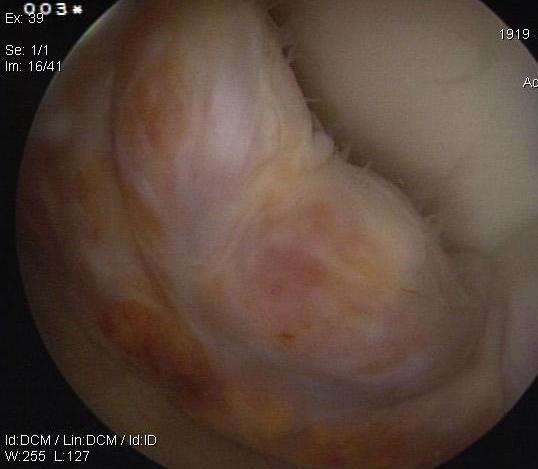

Arthroscopy

Localized / nodular PVNS anterior knee joint

Localized / nodular PVNS posteromedial compartment knee

Diffuse knee joint